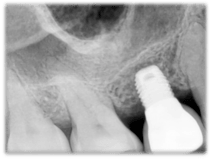

Historically, most research publications on successful implants were based on implant lengths of at least 10mm. Consequently, at least 10mm of bone is required to house the implant and that has resulted in the need for procedure such as the sinus lift to recreate the lost supporting bone structure. However, with advances in understanding of the process of how bone bonds with implants, implant designs have improved, both in terms of the macro design such as the screw threads as well as micro features such as the surface properties, implants shorter than 10mm have been found to be just as successful. Today, most of the major implant manufacturers have implants that are shorter than 10mm in their product range. They range from 5mm to 8mm. To compensate for the shorter length, implant surface is roughened to increase the bone to implant contact, the screw thread are made more aggressive to engage whatever little bone there is and the placement protocol has evolved into less drilling to preserve as much of the bone as possible. Hence, patients who have say 7mm of bone height can be treated with 7mm implants instead of having to have a sinus lift to add another 3mm of bone for a 10mm implant.